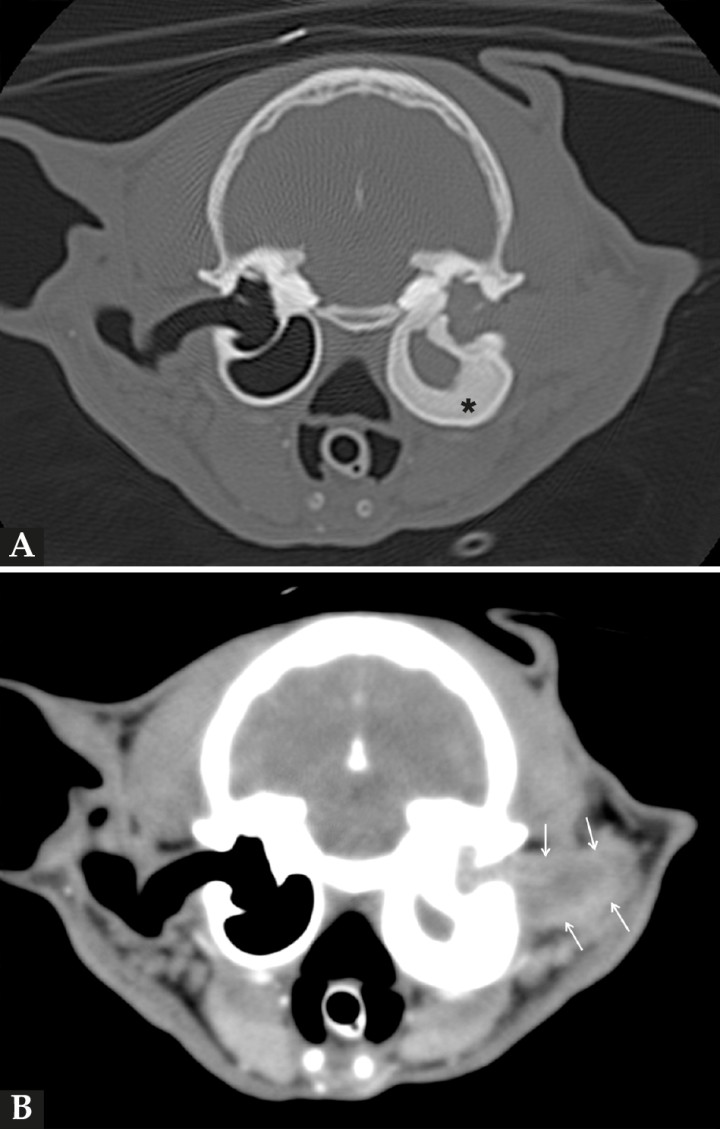

Para evaluar con mayor precisión la lesión y planificar el tratamiento quirúrgico es recomendable realizar una tomografía computarizada (TC).

En este caso, el estudio de TC (General Electric HiSpeed dual, General Electric Healthcare, Madrid) se realizó bajo anestesia general y con el paciente en decúbito esternal. Se realizaron series pre y postcontraste (Iobitridol 300 mg I/ml; a dosis de 600 mg I/kg intravenoso, administrado de manera manual) tras su administración y pasados tres minutos (Fig. 3), con cortes de 3 mm de grosor e intervalo de 1,5 mm con algoritmo estándar (tejido blando) y hueso. El estudio de TC se evaluó en ventana de tejido blando y hueso. En la serie precontraste se visualizó la pared de la BT izquierda gravemente engrosada (5 mm) en comparación con la contralateral (1 mm), y su interior ocupado, casi en su totalidad, por un material de atenuación tejido blando (70 UH) que se extendía a lo largo de la parte horizontal del CAE, teniendo una menor atenuación (38 UH), pero con bordes más atenuados (60 UH). En la imagen inmediata a la administración del contraste se observó un moderado realce periférico o en anillo de la masa (75 UH), mientras que su interior apenas mostraba captación de contraste (44 UH). Pasados tres minutos, el realce se incrementó ligeramente en la periferia de la masa (90 UH) manteniendo una atenuación prácticamente similar en su interior (50 UH).

Figura 3

Imágenes de tomografía computarizada (TC) en plano transversal en ventana de huesos (A) y en ventana de tejidos blandos tras la administración de contraste (B) de la cabeza del paciente, en las que se visualiza severo engrosamiento y esclerosis de las paredes de la bulla timpánica izquierda (asterisco), cuyo interior se encuentra ocupado por material de atenuación tejido blando que se continúa hacia el conducto auditivo externo en el que se aprecia realce postcontraste de manera periférica (en anillo) (flechas).

Estos hallazgos eran compatibles con un PIA con ocupación de la BT y CAE izquierdo, asociado a una severa esclerosis de la pared de dicha bulla.

Por otra parte, la TC aporta una mayor información anatómica y permite diferenciar el contenido de la BT por su atenuación (UH). El patrón de TC característico del PIA es el de una masa bien definida y pedunculada con marcado realce en anillo tras la administración del contraste. Con respecto a la resonancia magnética, puede ser una herramienta ventajosa, sobre todo en aquellos casos en los que haya sospecha o sintomatología compatible con enfermedad neurológica.3,4 En el presente caso, las pruebas de imagen permitieron apreciar una lesión compatible con un PIA, poniendo de manifiesto una grave esclerosis de la pared de la BT izquierda.